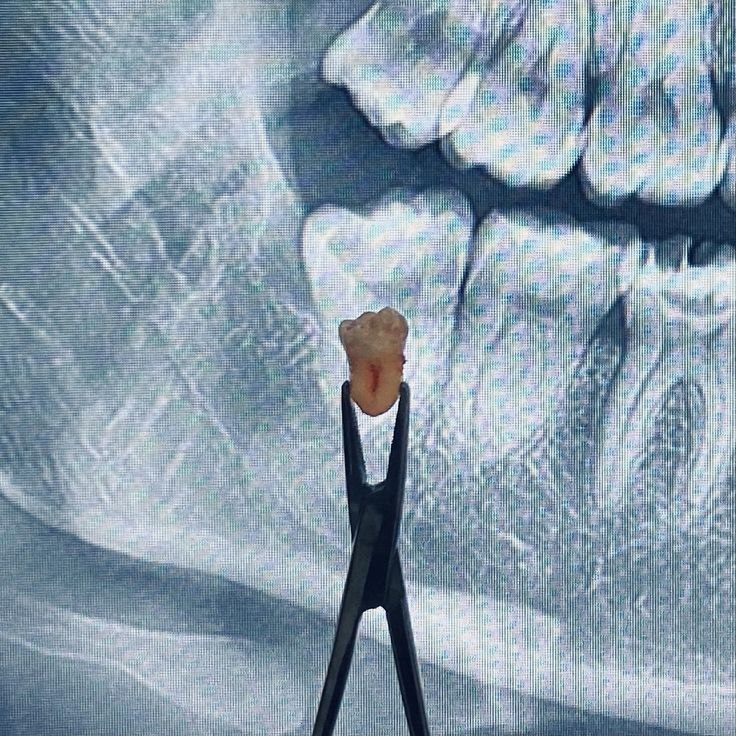

کشیدن دندان: نکات و مراقبت‌های ضروری برای بهبودی سریع

کشیدن دندان عقل و سایر دندان ها